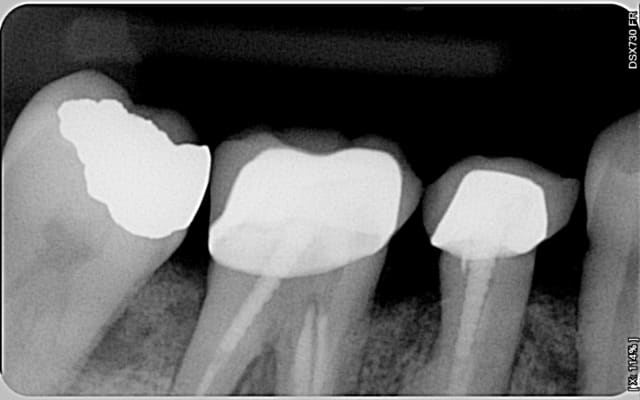

Je te montre quelques cas cliniques traités avec Emdogain et sans matériaux de comblement sur lesquels j'ai plusieurs années de recul :

Cas 1

Initial 46 th2se3 - Eugenol

Final 46 s2gxlk - Eugenol